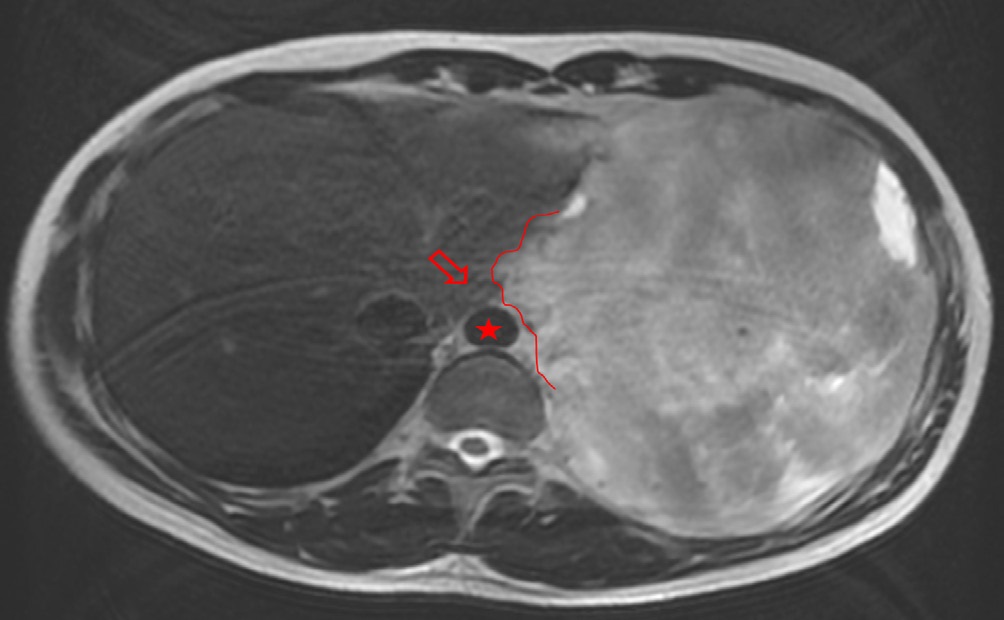

The patient presented with voluminous and symptomatic disease less than six months of chemotherapy end and less than two months of radiotherapy. He restarted with pain in left hemithorax, cough, shortness of breath, lack of appetite and daily vespertine fever. MRI scans in August, 2021 showed new lesions on pleural surfaces beyond the residual mass previously seen (Figures 4a, 4b and 4c). One of the lesions, on the extra-pleural fat adjacent to the diaphragm, extended inferiorly, pushing downward the muscle.

Before opting for some new agent, empirically, a next generation sequencing analysis was performed on the primary tumor tissue, to guide the subsequent therapy. An amazing pathogenic HMBOX1-ALK gene fusion was identified. Thus, we decide to continue his treatment by administering crizotinib, a tyrosine -kinase inhibitor (TKI) approved in Brazil for usage in lung cancer with ALK translocation. At the beginning of oral therapy, he manifested nausea grade 2, vomit grade 1 and diarrhea grade 2, according to WHO (World Healthy Organization) profile toxicity; all of these symptoms were manageable with regular antiemetic drugs and loperamide. Approximately, one month after the beginning of the new treatment, he reported reduction of chest pain and cough, as well as diminishing of tiredness and dyspnea, which were present only with great effort. The evaluation images with 45 days of crizotinib therapy showed reduction of all the lesions with appearance of necrotic/hemorrhagic areas (Figures 5a and 5b).